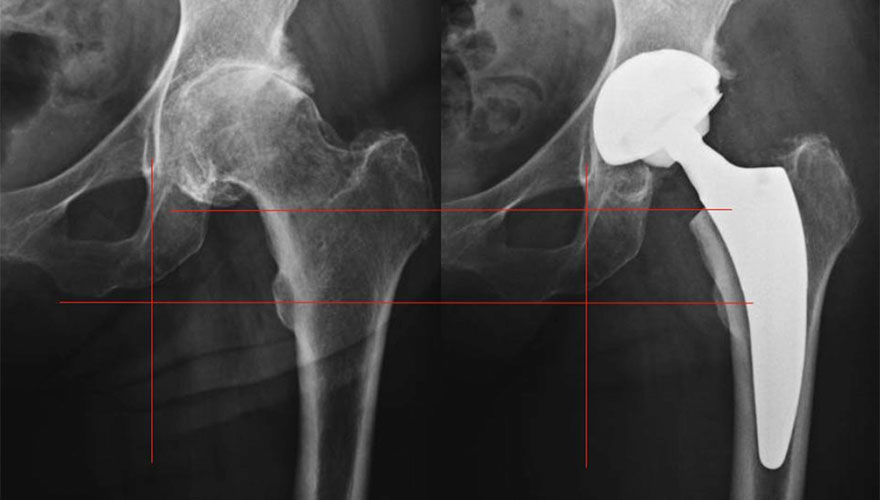

Für den betroffenen Patienten bedeutet dies eine Einschränkung der Mobilität und zunehmend schlechtere Lebensqualität. Sind alle gelenkerhaltenden konservativen und operativen Maßnahmen (Physiotherapie, Injektionen, Schmerzmedikamente, arthroskopische Gelenkspülung, usw.) ausgereizt, muss über das Einsetzen einer Totalendoprothese (TEP), einem Kunstgelenk, gesprochen werden. Am häufigsten werden Hüft- und Kniegelenke operativ ersetzt, immer öfter wird jedoch auch am Schultergelenk ein Teil- oder Komplettersatz durchgeführt. Auch kleinere Gelenke wie Ellenbogen- und arthrotisch zerstörte Fingergelenke (Handchirurgie) können mit Endoprothesen versorgt werden.